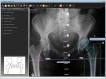

Objective: This study aims to provide a safe, reliable and reproducible method for prediction of acetabular component size based on measurement of the radiographic femoral head diameter, with the aid of templating software.

Methods: A defined methodology for femoral head measurement was applied to 97 consecutive, calibrated digital pelvic radiographs. Based on radiographic femoral head diameter, the minimum acetabular shell diameter was calculated and then compared to the size of the implanted acetabular shells.

Results: This method predicted safe minimum acetabular component size with an accuracy of 95.9% with a high inter-observer reliability of 97.6%.

Conclusions: This study presents a simple, reproducible and accurate method for templating of the minimum safest acetabular component diameter.